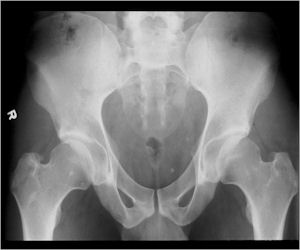

- Femoral neck most common but can occur in any bone and any site within a bone (metaphyseal, diaphyseal, epiphyseal; cortical, medullary and periosteal)

- 50% occur in long bones of lower extremities

- Intracapsular osteoid osteomas are difficult to identify because there is no periosteum in the intracapsular region and hence a periosteal reaction does not occur.